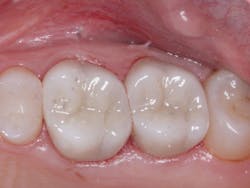

A: Full-zirconia restorations have been available for the past years or so. They have evolved from relatively unesthetic, opaque crowns and bridges to significantly improved restorations with acceptable esthetics (figures 1 and 2). Most dentists have noted that the majority of zirconia restorations are lighter in color than they requested on their lab order. The intense opacity of this material makes the restorations appear light in color. As the new generation of "esthetic zirconia" restorations continues to improve, this color problem will probably be overcome.

Figure 1: These full-zirconia fixed prostheses have served in the mouth for three years. Clinicians Report Foundation has research (TRAC Division) on zirconia-based three-unit fixed prostheses now serving for nearly 12 years.

Figure 2: Full-zirconia restorations on the first and second molars show the significant improvement in color now available with full-zirconia restorations.